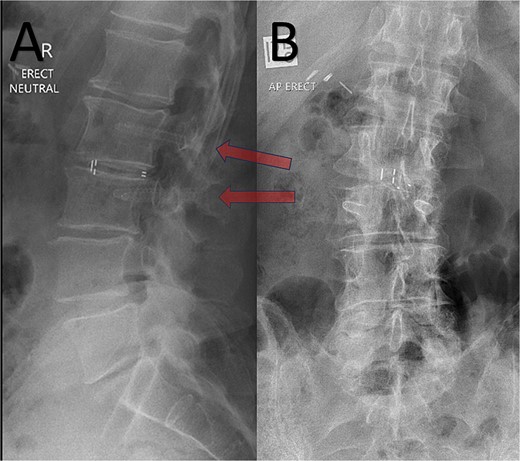

A 72-year-old male with a history of bowel cancer presented with severe discogenic back pain and lumbar instability at L2/3 requiring surgical intervention. The patient had previously been diagnosed with bowel cancer and although was clear of tumor load after prior surgery, the oncology team informed that further recurrence of disease was likely, and potentially a candidate for adjuvant radiotherapy and chemotherapy in the future. Given the potential need for repeat imaging and precision radiotherapy, the oncology and surgical teams opted for spinal fixation with carbon-based pedicle screws and rods. The patient underwent an uneventful L2/3 posterior lumbar fusion with the placement of carbon-fiber pedicle screws (Matrix Medical Innovations, Australia) and PEEK interbody implant (ASpine, Taiwan). Postoperative imaging, including the attached X-ray (Fig. 1), and demonstrated excellent screw positioning and spinal alignment. The radiolucent nature of the screws resulted in minimal disruption of the radiographic field, a stark contrast to the typical imaging artifacts associated with metallic implants. The patient experienced an uneventful recovery, with resolution of his discogenic back pain and no perioperative complications. Follow-up imaging showed continued alignment and no radiographic interference, allowing seamless planning for subsequent radiotherapy should this be necessary.

Post-operative erect XR lumbar spine after L2/3 lumbar fusion. Arrow = CFRP pedicle screws. A – Sagittal; B – Anteroposterior views.

In this case, the use of carbon-based screws facilitated both effective spinal stabilization and enhanced radiotherapy planning should this be necessary, providing a dual benefit. The postoperative imaging (Fig. 1) underscores the radiological advantages of these implants, as the screws are nearly invisible, preserving the clarity of adjacent structures.